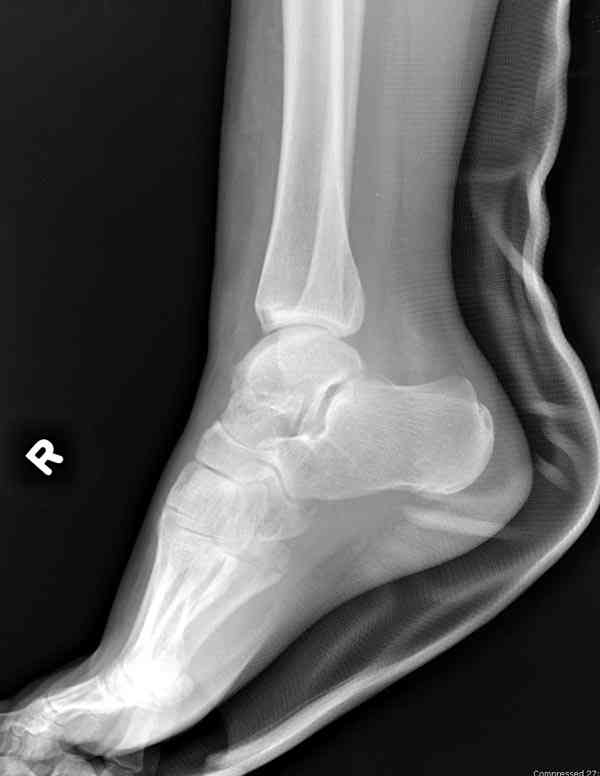

Для оценки состояния нужны дополнительные исследования, например

> Canale или Broden ренгенограммы

повторили рентгенограммы и доделали проекции, к единому мнению все еще не пришли